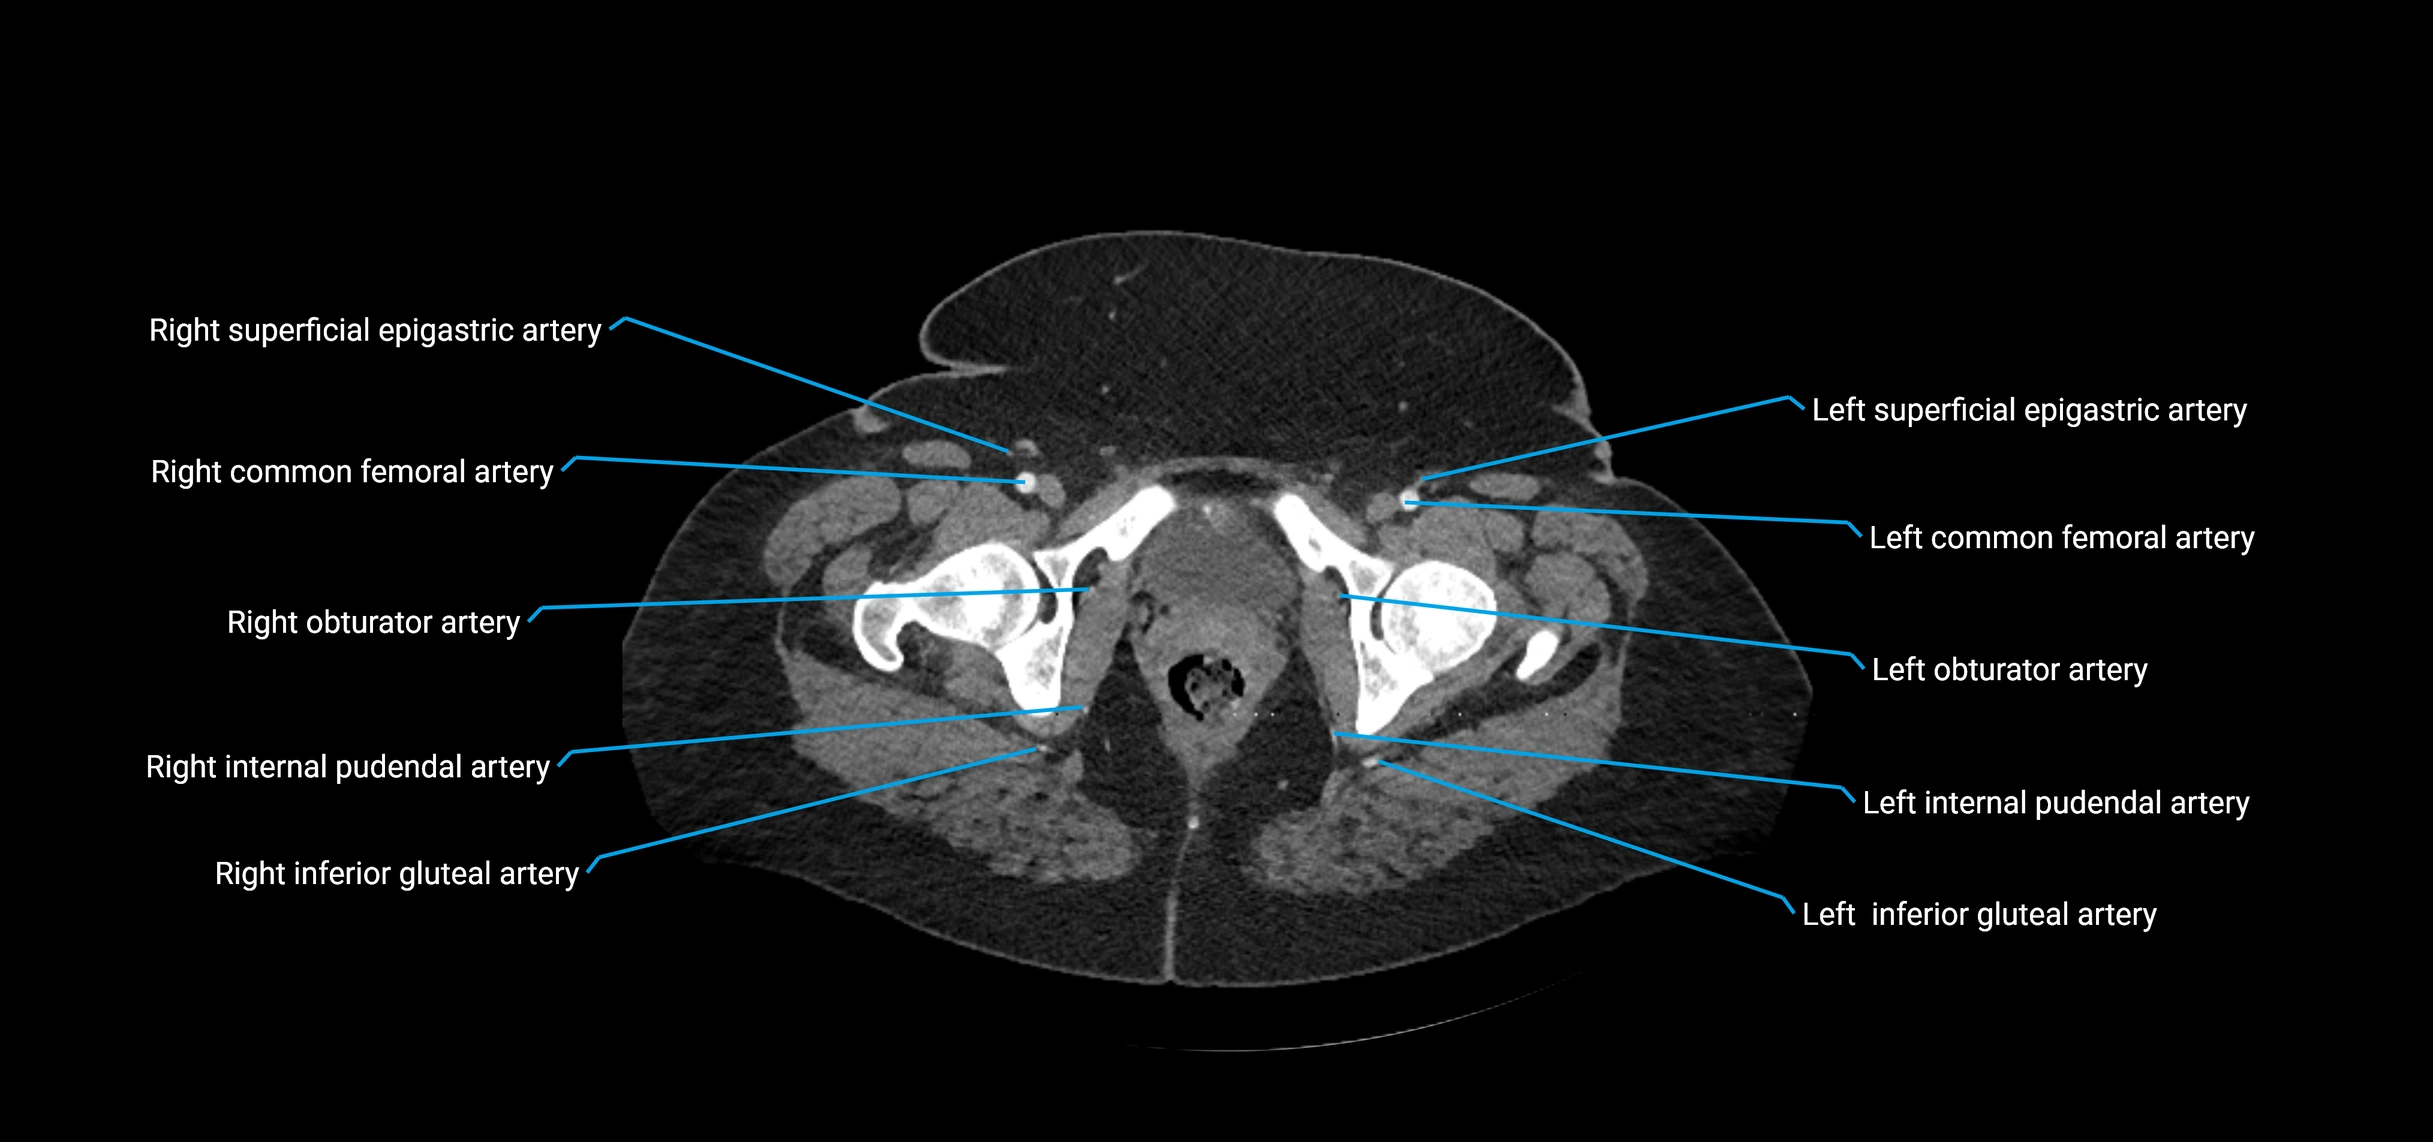

Contrast-enhanced CT (CTA):

• Gold standard for abdominal aortic imaging

• Provides excellent detail of lumen, wall, aneurysm, thrombus, and branch vessels

• Multiplanar and 3D reconstructions help in aneurysm measurement, stent graft planning, and dissection evaluation